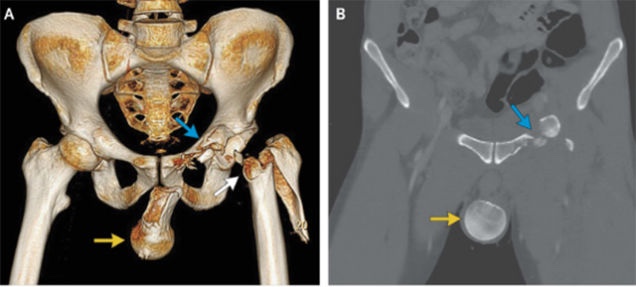

Man's Femur Goes Into His Ballsack After Motorcycle Crash [NSFW]